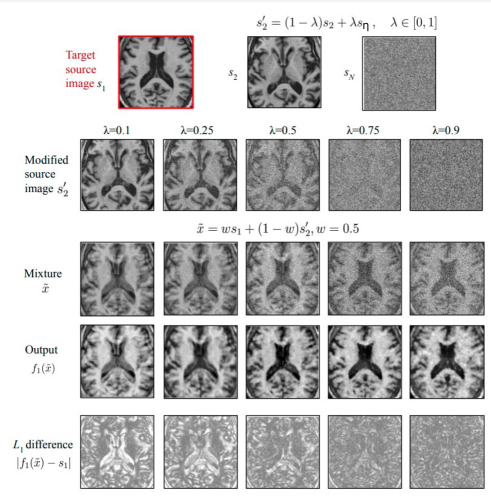

Refer to caption

Fig. 1: Qualitative results of recovering s1subscript𝑠1s_{1} with various λ𝜆\lambda. We can see that the model is able to separate and reconstruct s1subscript𝑠1s_{1} from x~~𝑥\tilde{x} gradually when λ𝜆\lambda increases from 0.1 to 0.9. The dataset in this experiment contains 30 brain MRI scans from 30 different patients. Best viewed with zoom.

In this small experiment, for a given medical imaging dataset, DIsubscript𝐷𝐼D_{I}, we randomly sample two source signals (images), s1subscript𝑠1s_{1} and s2subscript𝑠2s_{2}, for every training iteration and linearly ‘mix’ them. The mixed signal is fed as input to a neural network while s1subscript𝑠1s_{1} is set as the source to be reconstructed by the network. As can be observed, we have M~=N~(=1)~𝑀annotated~𝑁absent1\tilde{M}=\tilde{N}(=1) in this case, and the sources are sampled from the same distribution, which render this ill-posed.

One way to make the reconstruction task less ambiguous would be to sample signal s2subscript𝑠2s_{2} from a different domain than s1subscript𝑠1s_{1}, for instance by adding noise to s2subscript𝑠2s_{2}, as follows:

s2=(1λ)s2+λsη,λ[0,1]formulae-sequencesubscriptsuperscript𝑠21𝜆subscript𝑠2𝜆subscript𝑠𝜂𝜆01s^{\prime}_{2}=(1-\lambda){s_{2}}+\lambda{s_{\eta}},\quad\lambda\in[0,1] (5)

where sηk𝒩(0,1)similar-tosubscript𝑠𝜂𝑘𝒩01s_{\eta k}\sim\mathcal{N}(0,1) for the k𝑘kth voxel in sNsubscript𝑠𝑁s_{N}, such that when λ=1𝜆1\lambda=1, s2subscriptsuperscript𝑠2s^{\prime}_{2} is purely a Gaussian noise which belongs to an obviously different domain compared to the imaging domain in dataset DIsubscript𝐷𝐼D_{I}. The new mixture, x𝑥x, can be created by applying Equation (2) on s1subscript𝑠1s_{1} and s2subscriptsuperscript𝑠2s^{\prime}_{2}, and the loss to be minimized by the neural network can be calculated using Equations (3) and (4) by setting M~=N~=1~𝑀~𝑁1\tilde{M}=\tilde{N}=1.

The results of a neural network (we use 2D UNet [39] here) optimized to minimize the reconstruction loss of s1,s2subscript𝑠1subscriptsuperscript𝑠2s_{1},s^{\prime}_{2} with various value of λ𝜆\lambda are visualized in Figure 1. It can be observed that when λ𝜆\lambda is small (0.1), the output is an average of the two images s1subscript𝑠1s_{1} and s2subscript𝑠2s_{2} and the model fails to separate s1subscript𝑠1s_{1} from the mixture, x𝑥x. When λ𝜆\lambda gradually increases (to 0.9), s1subscript𝑠1s_{1} becomes clearer and better separated.

As this experiment illustrates, the network can not separate sources when they are sampled from the same distribution and mixtures are made arbitrarily. To impose extra constraints and increase separability, one simple way is to sample sources from different domains, for instance an MRI scan and Gaussian noise. However, the case λ=1𝜆1\lambda=1 is similar to a self-supervised denoising task where the model may focus on learning the differences between image domain and noise domain. These learned features may contain trivial local patterns and may be less likely to provide useful semantic features for downstream tasks like segmentation. The technique that we propose next relies on creating more mixtures than samples to be extracted, such that M~>N~~𝑀~𝑁\tilde{M}>\tilde{N}, by always having a fixed source in all of the mixtures created, such that the network can get extra information to help it identify this desired (fixed) source. We name the former variant as Denoising SI (DSI) and the latter variants are Cross-patients SI (CSI) and Within-patients SI (WSI), depending on which sources are mixed. We describe these variants in detail in the forthcoming sections.